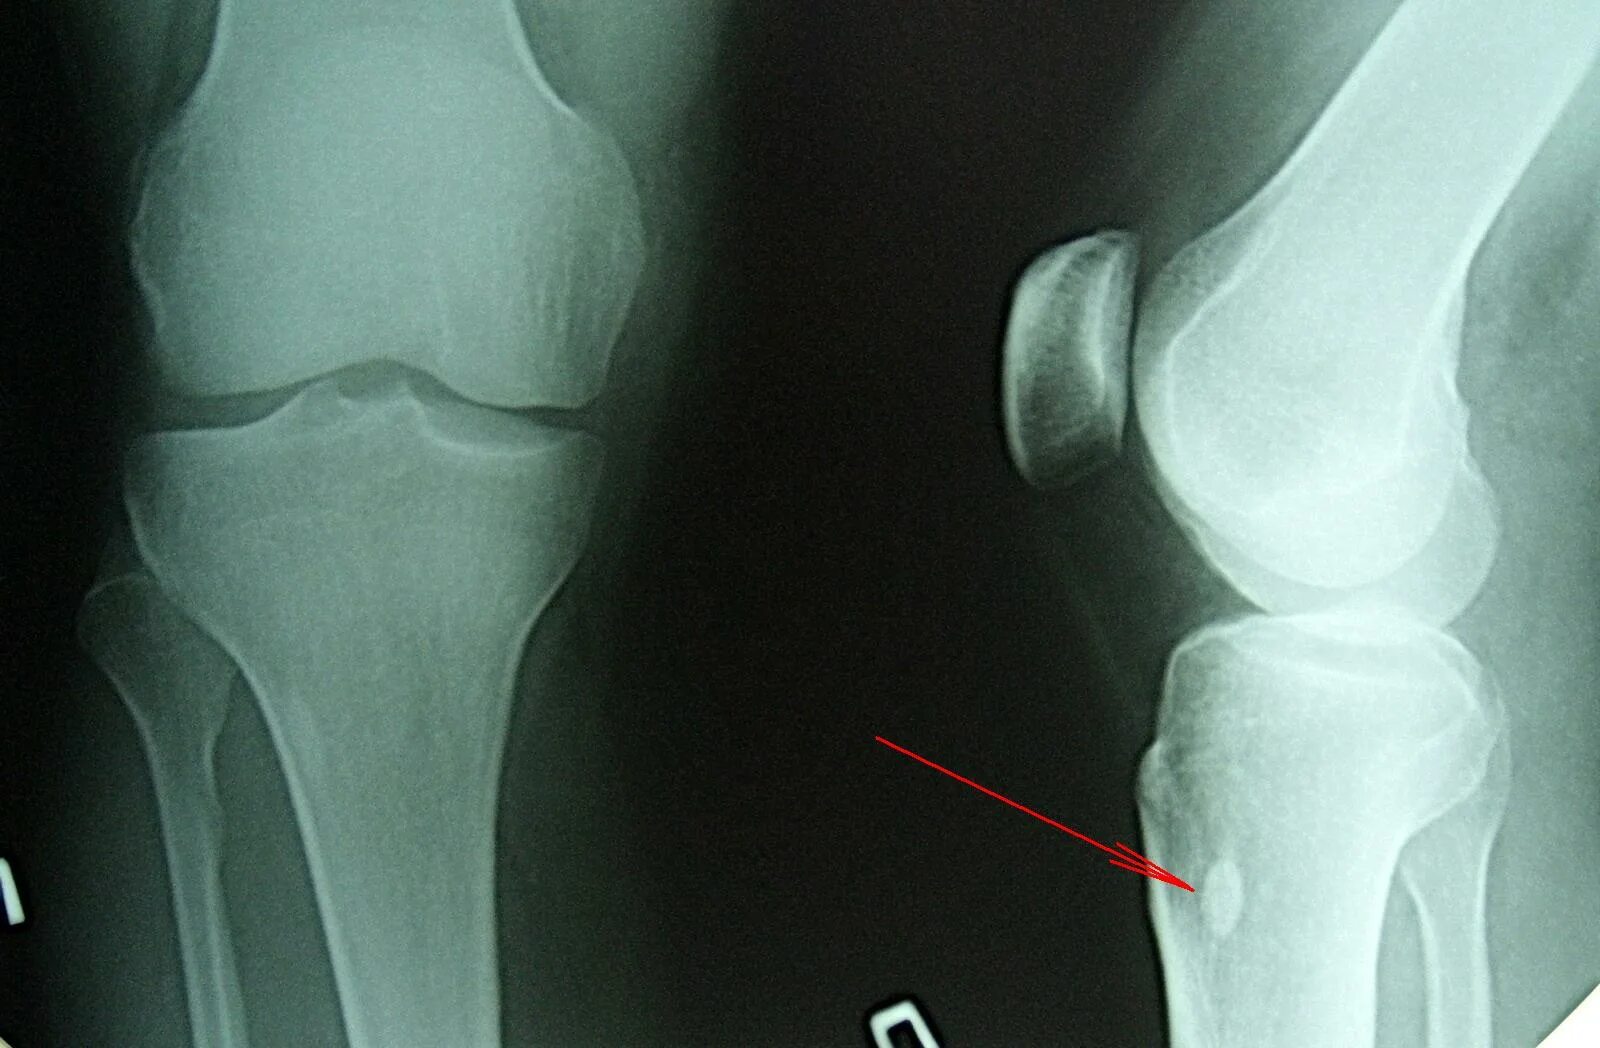

Перелом коленного сустава мкб